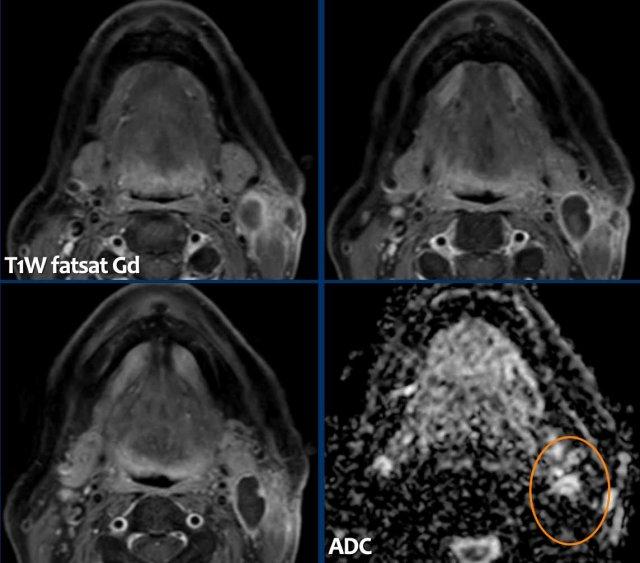

Ung thư biểu mô tuyến

Đây là bệnh nhân có triệu chứng nghẹt mũi tắc nghẽn.

Nếu chỉ mô tả ca này đơn thuần là hình ảnh mờ gần hoàn toàn các xoang cạnh mũi bên phải, bác sĩ lâm sàng có thể dễ dàng nghĩ đây chỉ là một trường hợp viêm xoang thông thường.

Như đã đề cập, dấu hiệu cảnh báo ở đây chính là vị trí định khu bất thường một bên.

Viêm xoang một bên là cực kỳ hiếm gặp.

Hơn nữa, nếu quan sát kỹ, có thể thấy hình ảnh phá hủy vách ngăn mũi — đây là dấu hiệu cảnh báo thứ hai.

Tiếp tục xem hình ảnh MRI…

Hình ảnh MRI cho thấy một khối u một bên trong hốc mũi phải gây tắc nghẽn xoang trán và ở mức độ thấp hơn là xoang hàm.

Có hiện tượng hạn chế khuếch tán (tăng tín hiệu trên DWI và giảm tín hiệu trên ADC) — đây là dấu hiệu cảnh báo thứ ba.

Sinh thiết xác nhận ung thư biểu mô tuyến.

Bệnh nhân được điều trị bằng phẫu thuật cắt bỏ kết hợp xạ trị proton và hiện không còn bằng chứng bệnh trong 14 tháng.